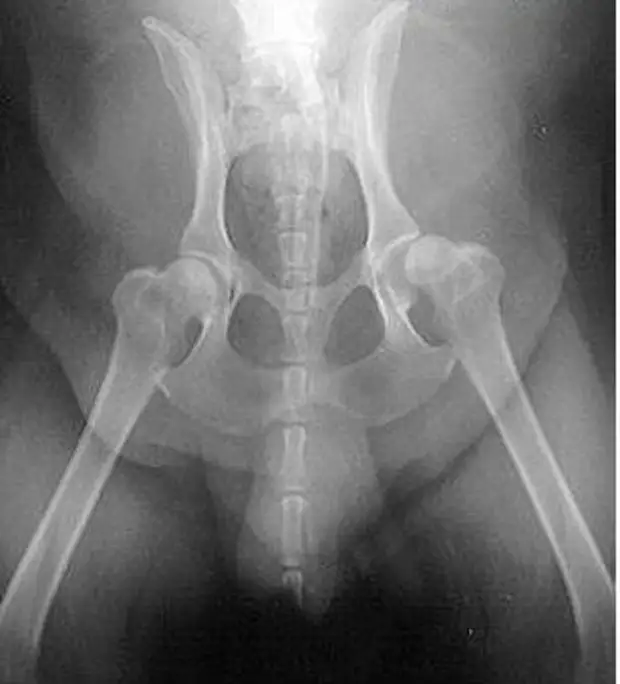

Рентгенограммы таза взрослой собаки с нормальными тазобедренными суставами, сравните их с приведенной ниже собакой с дисплазией тазобедренного сустава

У этой собаки умеренные изменения, указывающие на дисплазию бедра с обеих сторон.

Гнезда не такие закругленные, как должны быть, а головка бедренной кости немного приплюснута.

Рентгенограммы должны выполняться под седалгией или под наркозом, чтобы обеспечить нужное положение сустава. Стандартный рентгенографический снимок делается, когда собака находится в дорсальном положении с вытянутыми параллельно задними конечностями, колени повернуты так, чтобы коленная чашечка находилась в центре блоковой борозды и симметрично расположенным тазом. Вентродорсальный вид должен включать два поясничных позвонка и оба колена. Тяжесть клинических симптомов не соотвествует тяжести рентгенографических изменений. Рентгенографическая съемка под нагрузкой поможет количественно оценить степень слабости сустава.

Стандартный вид: кошка лежит на спине, а ее задние лапы вытянуты прямо. Этот вид похож на оценочную рентгенограмму, необходимую для подтверждения OFA степени дисплазии бедра. (OFA классифицирует бедра по семи различным категориям: отличное, хорошее, удовлетворительное, пограничное, легкое, умеренное или тяжелое.) Для сертификации PennHIP выполняются дополнительные обзоры, которые учитывают измерения дряблости суставов, а также конформации тазобедренных суставов.